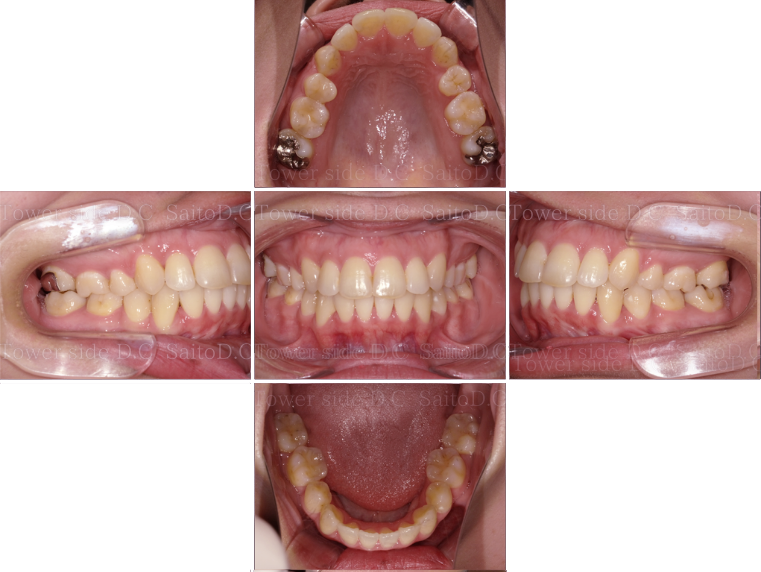

症例9CASE 9

|30代歳(女性)|

ワイヤー矯正

症例(施術前)

症例(施術後)

主訴 上前歯が出ている、上下前歯のガタガタが気になる

状況

• 上顎前歯前突

• 上下顎叢生

• 口唇閉鎖不全有

治療費 880,000円(税込)(自由診療)

治療期間 2年5ヶ月

治療内容 14.24.35.45を抜歯し、ワイヤー矯正にて咬合改善を行った。叢生、臼歯部噛み合わせは改善され、その後保定装置(リテーナー)を使用し安定している。